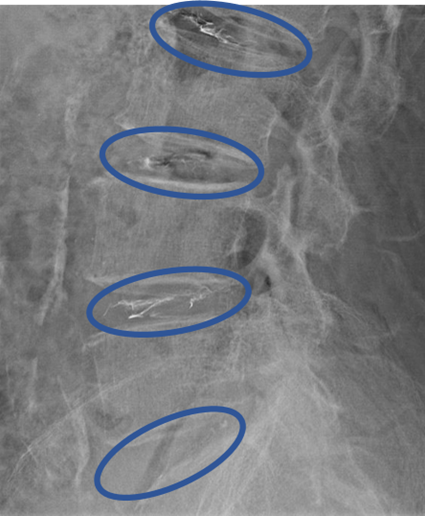

L2/3、3/4、4/5、5/s に

椎間板変性、椎間板膨隆、繊維輪断裂 を認め、主症状の原因の可能性が高い。

DiscoGelを入れた後の画像になります。

治療は 40分程度で終了